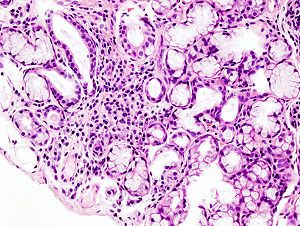

Patients with Sjogren’s syndrome are nearly 19 times more likely to develop lymphoma, so identifying factors that impact this risk development is a major goal in caring for this disorder. Many risk factors are established such as low C4, palpable purpura, parotid gland enlargement, and monoclonal gammopathy.